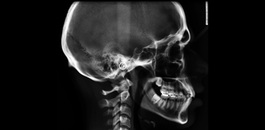

Documentação composta de radiografias, fotografias, modelos e análises cefalométricas com o objetivo de realizar um estudo detalhada da interrelação das estruturas dento faciais do paciente. Possibilitando a escolha do tratamento correto para o mesmo. Indicação: Tratamentos Ortodônticos e Ortopédicos.

Indicada para realização de análises cefalométricas. Sendo possível a avaliação das estruturas ósseas e respectivas interrelações. Muito indicada para planejamentos ortodônticos e ortopédicos.